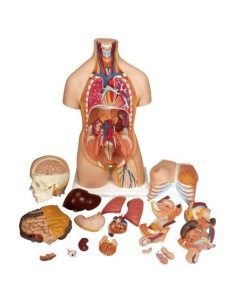

3B Torse scientifique, africain bisexuel, décomposable en 24 parties B37